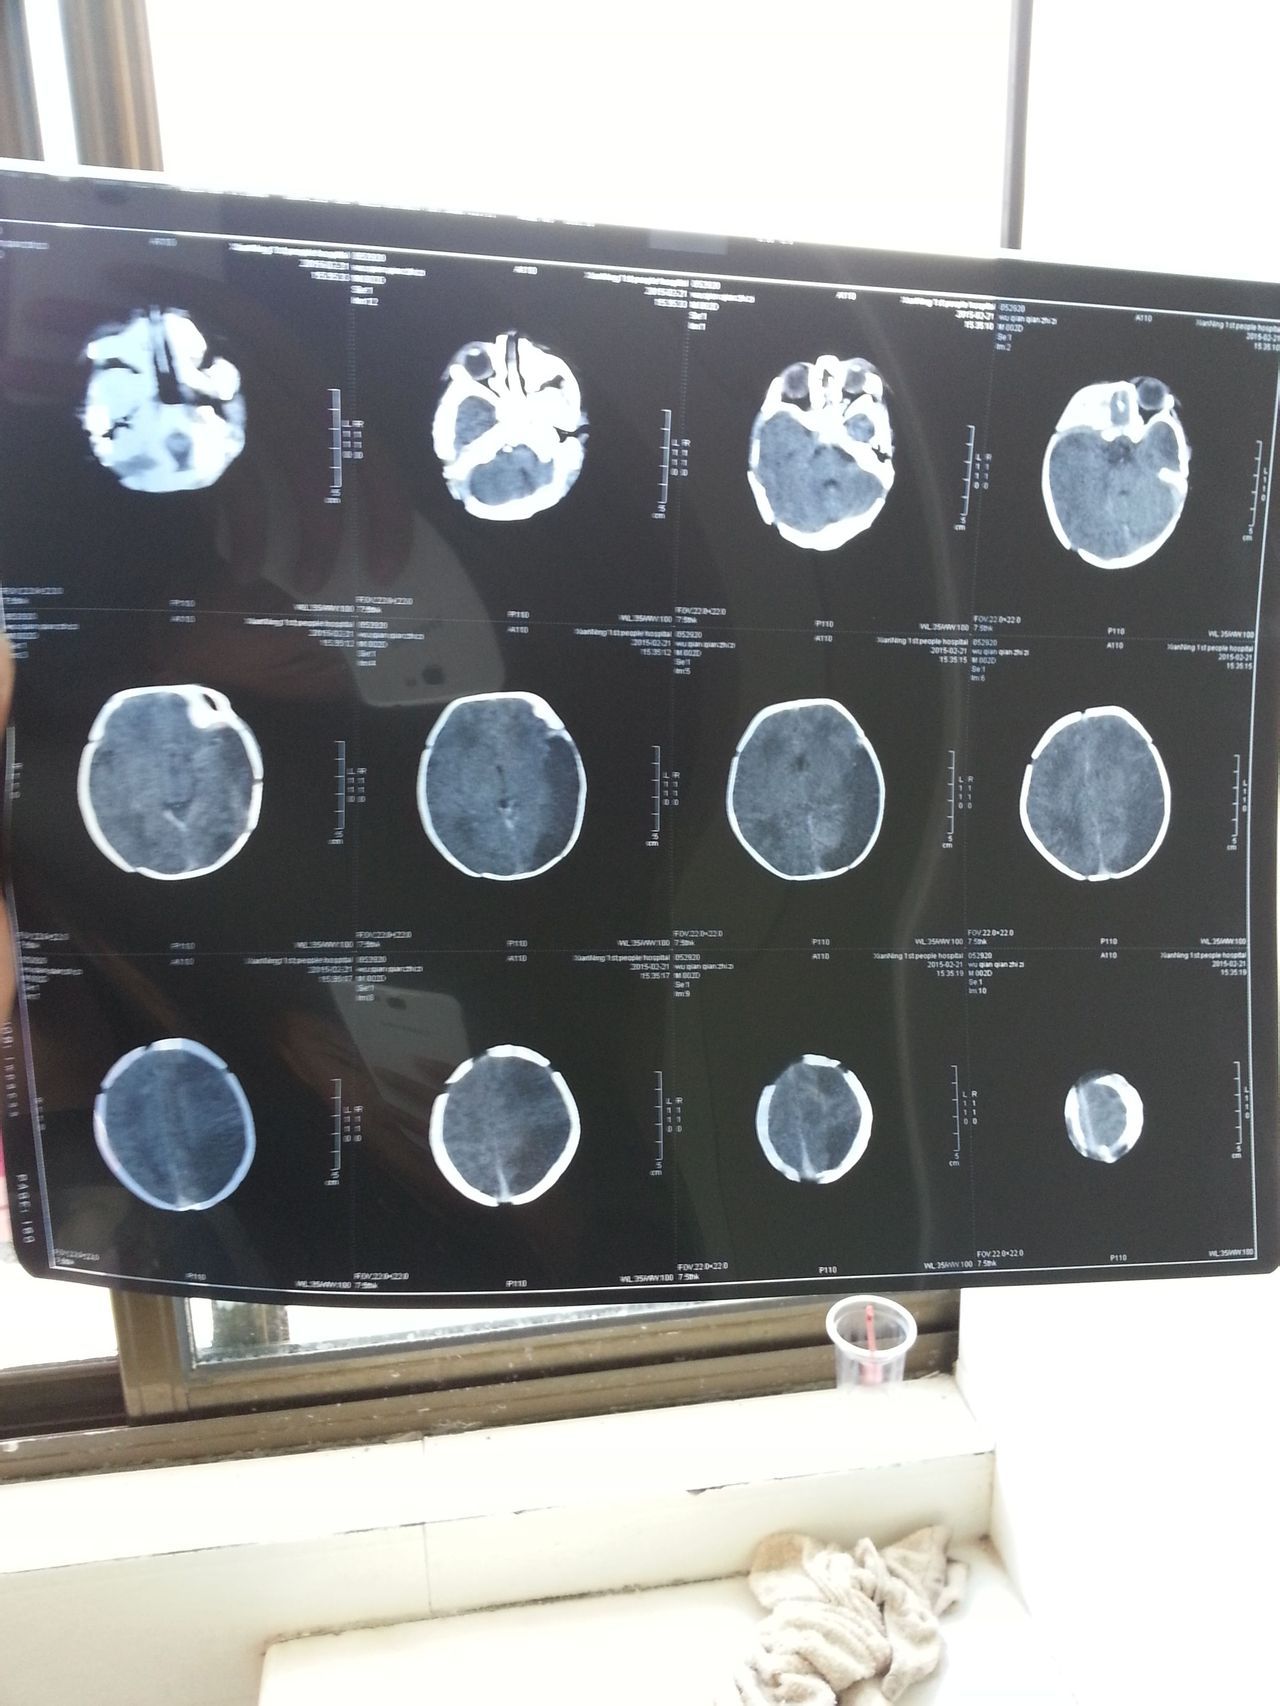

新生儿4天做CT和磁共振显示脑部有大片阴影,怎么办? 医生说可能是脑梗塞或者先天性脑血管畸形,请问真是这样,要怎么治疗,有康复的可能吗、万分感谢 点击展开 匿名用户 2015-02-23 19:45 为您推荐: 其他回答 您好,根据您所提供的资料,您最好去全国有名的大医院看看,除了提高诊断的水平,还可以在治疗上有帮助。 cn#GkpuLLLVG 2015-02-23 23:00 相关问题 我6月25号来月经,7月10 做腿 胸部X光,脑部CT,14号做磁共振等检查,8月25 好发现怀孕了,BB还能要吗 新生儿败血症ct脑部未发现血块 还必须要做要穿吗?还有血培养还没出来来,医生说临床就可以确诊败血症了 十岁孩子左脚走路向外歪,x线做两个脚脖,盆骨 CT做两个脚 磁共振做了脑部,腰椎,骨头,骨盆,神经